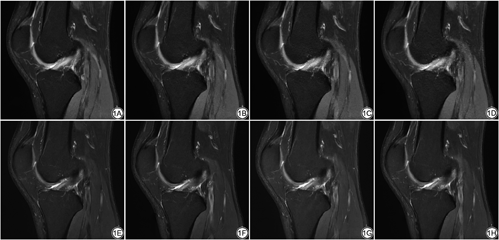

进一步对CS与ACS各序列的主观评分进行分析,并将5处组织SNR与PI 2.0进行两两比较,结果见表2。CS 2.0、ACS 2.5、ACS 3.0图像质量医师主观评分与PI 2.0之间差异无统计学意义,CS 2.5、CS 3.0、ACS 3.5、ACS 4.0评分显著低于PI 2.0 (P<0.05)。两位医师对图像质量进行评分时发现随加速因子增大,CS序列图像噪声增加;ACS则表现为图像模糊(图1)。

本研究还注意到CS与ACS随加速因子增大,扫描时间缩短的同时医师图像质量主观评分逐渐降低,但CS与ACS评分降低的原因不尽相同。CS序列随加速因子增大,图像噪声增多,在最大加速因子CS 3.0中,噪声甚至导致部分组织显示不清。而ACS序列随加速因子增大,图像模糊程度增加,组织结构与细节显示不清。由于目前有关ACS图像质量评价的研究较少,本研究进行了加速因子对质子密度加权序列图像质量影响的研究,后续需要多种对比度、多中心研究的图像数据对这一现象及其原因进行探讨。